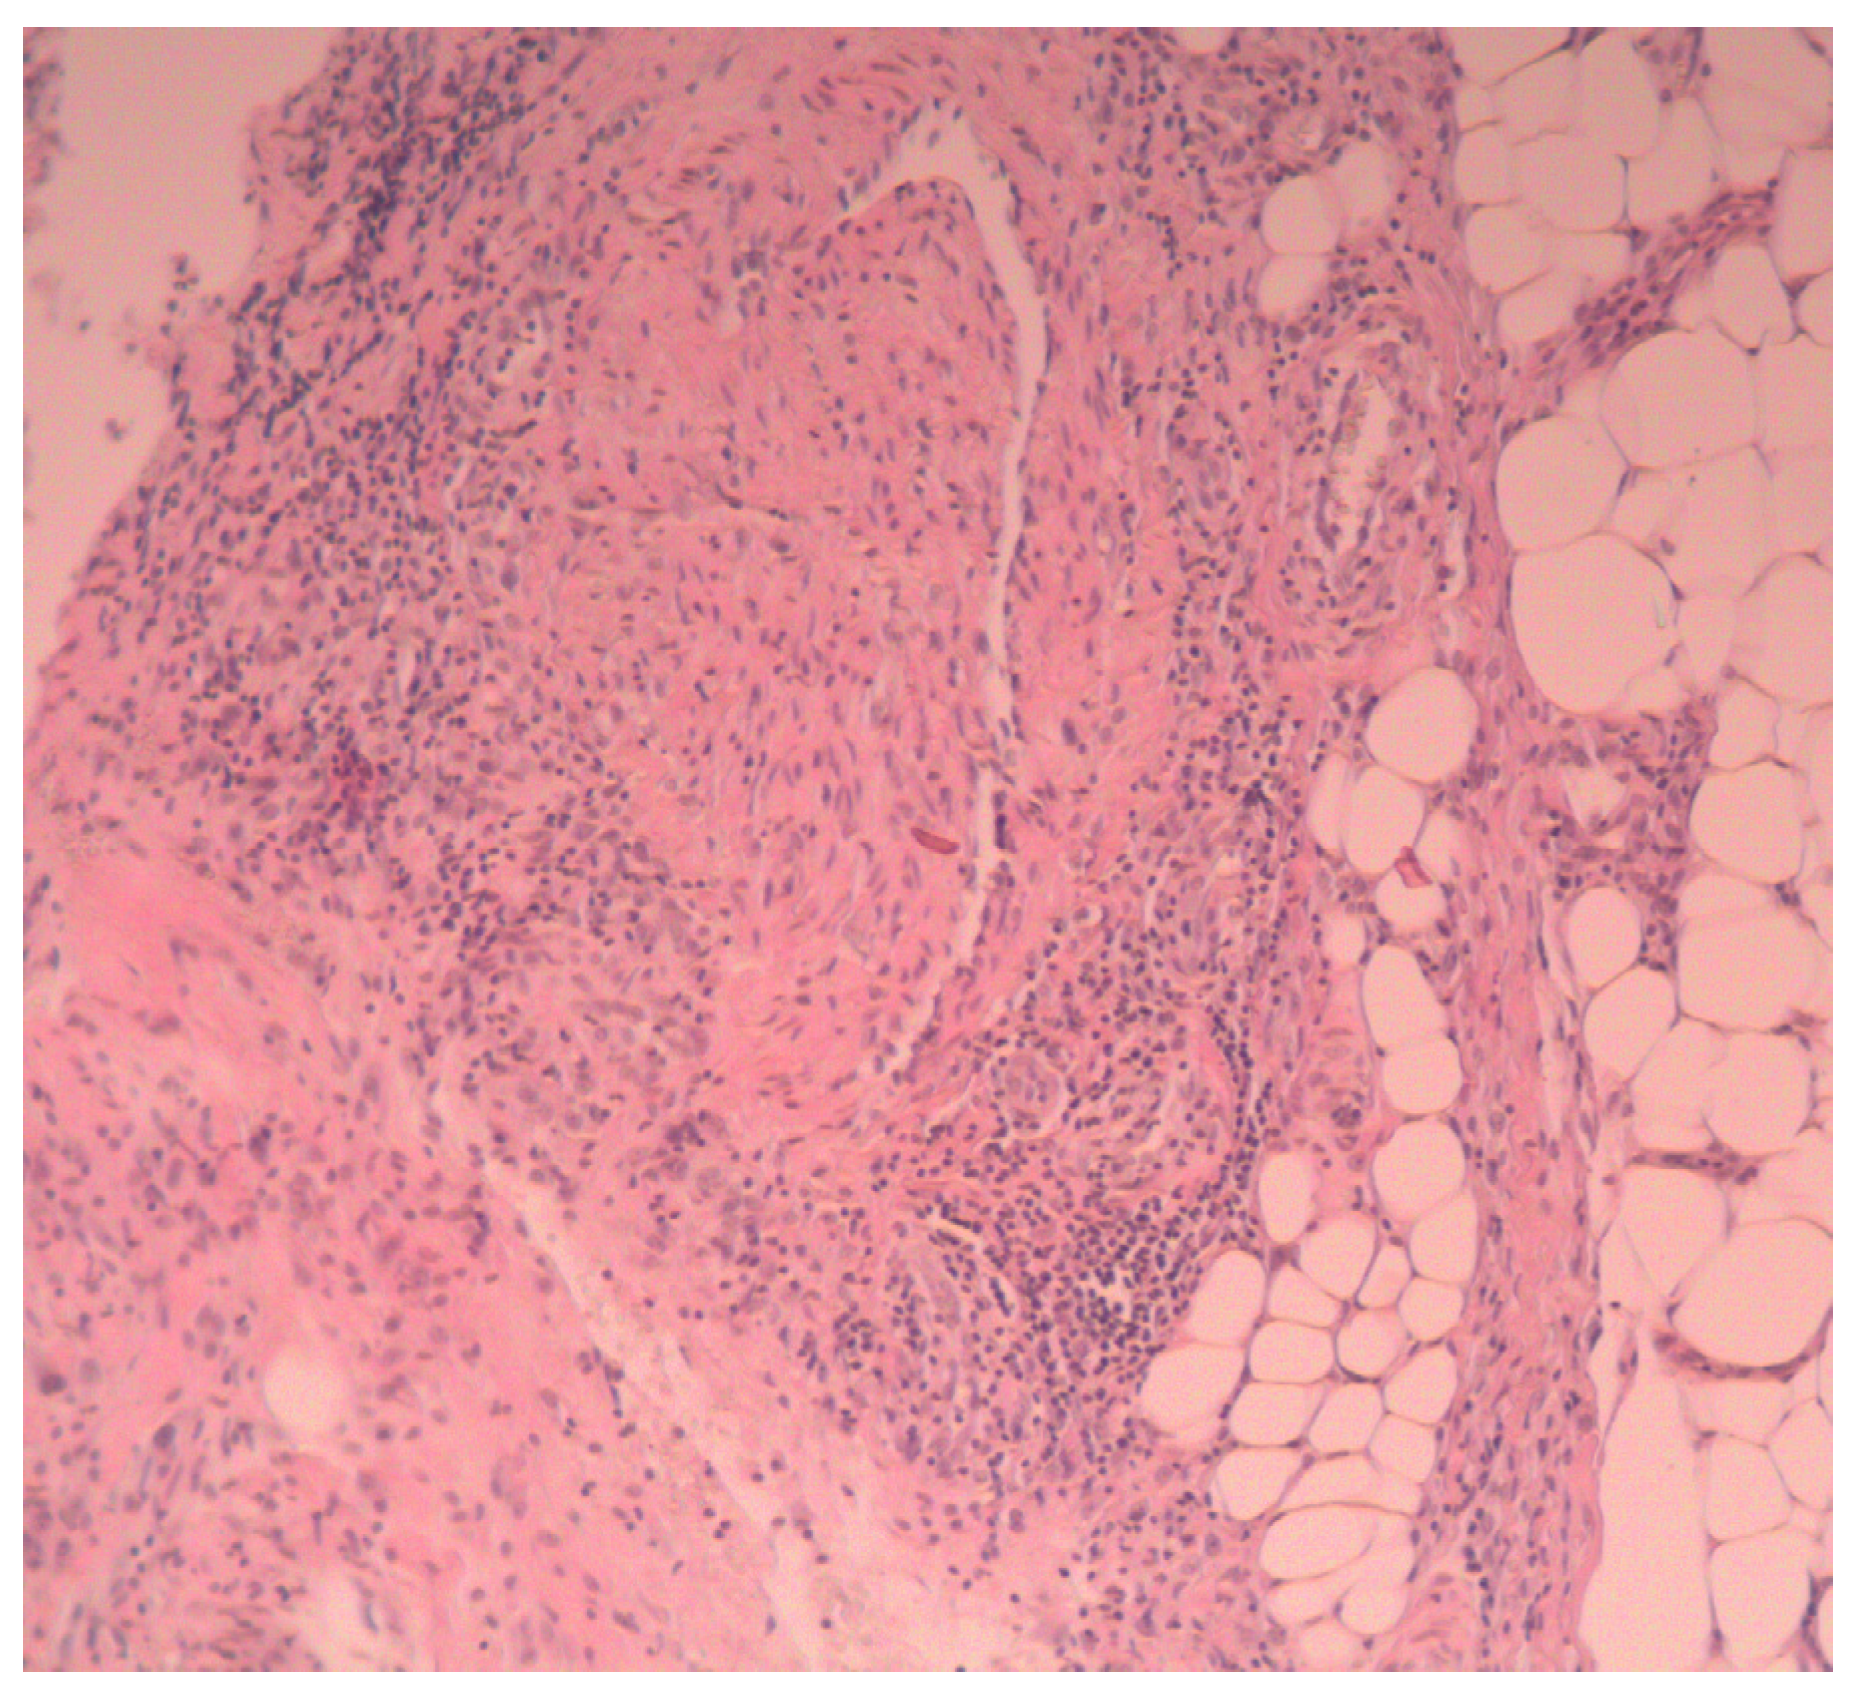

Histopathological examination is mainly aimed at excluding other conditions (e.g., deep mycoses), similar to other neutrophilic diseases. The subcutaneous tissue is affected by an abundant infiltration of mature PMNs in the center, with histiocytes and single giant cells present at the periphery. In the acute phase, neutrophils dominate, then the organization of the epithelial border with palisading histiocytes appears. Fewer neutrophils are observed throughout the late phase. They are surrounded by fibrous tissue with macrophages [2].

We performed a biopsy of an abscess of the right dorsum of the hand. Histopathological examination showed sparse infiltrates of mononuclear cells in the skin around the vessels, and acute inflammatory infiltration in the subcutaneous tissue (mainly neutrophilic), with necrotic foci, penetrating into the subcutaneous connective tissue (Figure 3).

Figure 3. Histopathological examination: acute inflammatory infiltration in the subcutaneous tissue, mainly neutrophilic, with necrotic foci, penetrating into the subcutaneous connective tissue.